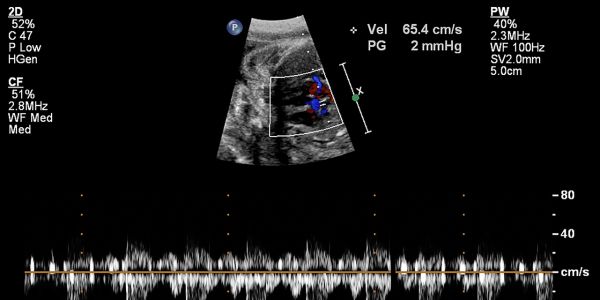

Ecocardiofetale: Prevenzione Cardiologica del Feto, cos’è e quando farla

L’ecocardiofetale è un esame ecografico che serve a valutare il cuore del feto durante la gravidanza.Si esegue nel secondo trimestre, tra la 20ª e la 24ª settimana, quando il cuore è già formato e può essere studiato nel dettaglio. È un’ecografia specialistica che si concentra solo sul cuore: ne analizza la struttura, il funzionamento, il […]